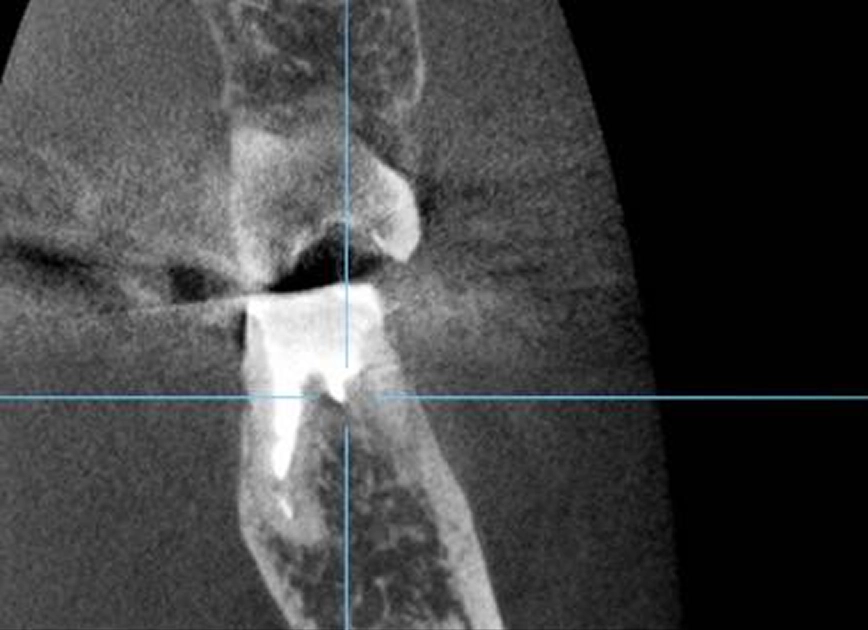

CTによる精密分析

CT撮影を行うことで、根管の形や方向、周囲の骨の状態を立体的に把握します。難しい症例や再治療の場合にも、安全で的確な処置を行うための重要な検査です。